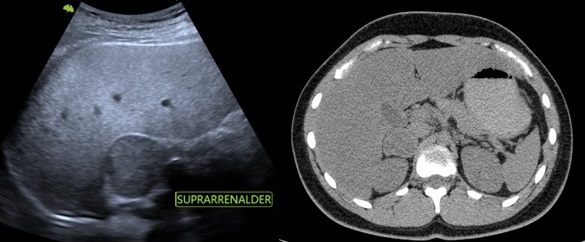

Se presenta el caso de un paciente masculino de 18 años sin antecedentes, que consulta por dolor en hipocondrio derecho de un año de evolución, asociado a palpitaciones, y episodios de HTA. El examen de orina de 24 horas mostró niveles elevados de catecolaminas. En la ecografía abdominopélvica y TAC abdominal, se objetiva una formación de aspecto nodular sólida hipoecoica de contornos bien delimitados, de aproximadamente 43 mm x 39 mm, que no muestra vascularización a la señal Doppler color, asociado a la TC abdomen con contraste EV: masa sólida de 38 mm x 31 mm, reemplazando el parénquima de la glándula suprarrenal derecha que realza de forma ávida y heterogénea en fase arterial a expensas de área central con degeneración necrótica. Se prepara con alfa bloqueador, se realiza adrenalectomía total izquierda laparoscópica. La anatomía patológica evidencia feocromocitoma.

El feocromocitoma es una entidad que afecta a pacientes jóvenes y tiene diversos hallazgos imagenológicos, siendo los más característicos por ecografía como masas grandes sólidas o quísticas con calcificaciones, de bordes bien definidos, dependiente de una glándula suprarrenal, en la TAC suelen ser heterogéneas, frecuente la calcificación, hemorragia y necrosis, con marcado realce tras la administración de contraste. Siendo este el gold standard con el protocolo de lavado suprarrenal se compone de una fase sin contraste, una exploración contrastada con un retraso de 60-90 segundos y una tardía a los 15 minutos con densidad > 10UH.